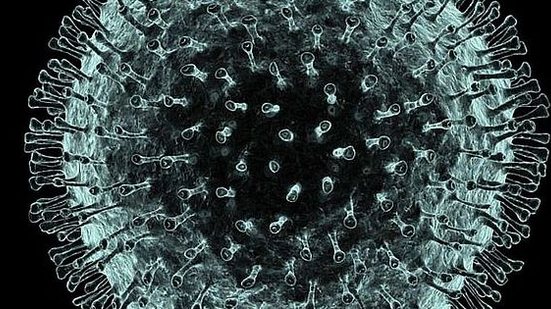

O total de mortos na China continental devido ao novo coronavírus aumentou hoje (10) para 908, mais 97 do que no domingo, informaram as autoridades.

Segundo números divulgados pela Comissão Nacional de Saúde da China, são agora 40.171 as pessoas infectadas no país.

Um aumento de 97 mortes indica um recrudescimento de casos do novo vírus, 2019-nCoV, depois de ter havido uma quebra no dia anterior.